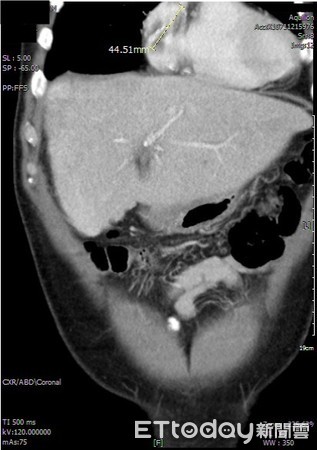

▲肝癌層層堆疊形成「癌栓」,會侵襲血管及淋巴系統。(圖/亞洲大學附屬醫院提供)

王博民分析表示,在肝癌腫瘤生長過程中,會層層堆積,所產生的「癌栓」約有1%至3%的機率,會脫落沿著血管流動跑到右心房,以致侵襲血管和淋巴系統,故肝癌晚期患者常為右心房或下腔靜脈血管阻塞的高風險族群,一般治療6周後有90%機率腫瘤會消一半以上;萬一心臟收縮將癌栓打入肺動脈,即可能呈現急性呼吸窘迫或衰竭、休克、昏迷等情形,嚴重時更可能猝死。